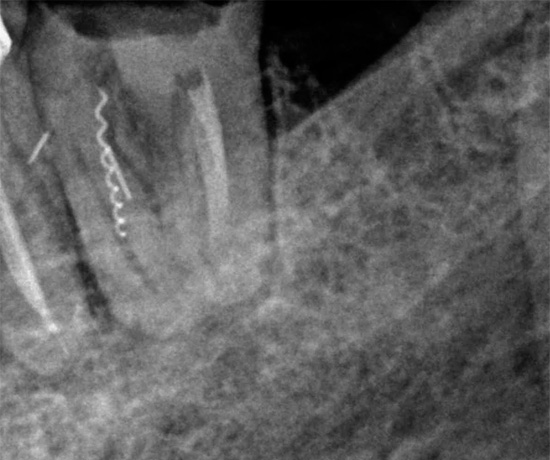

Lascando uma ferramenta em um canal

Se durante a limpeza do canal uma parte do instrumento endodôntico se romper nele, se for deixado no canal, o dente começará a doer imediatamente ou após algum tempo. Isso se deve ao fato de que um pedaço do instrumento preso no canal não dá ao médico acesso ao ápice da raiz, devido ao qual permanece uma parte do nervo ou uma infecção não tratada que começará necessariamente a se multiplicar e pode levar a problemas muito grandes no futuro.

Para evitar possíveis complicações futuras, a remoção imediata dos detritos é realizada usando vários métodos. Por exemplo, o método ultrassônico de "nocautear" um fragmento é atualmente usado ativamente. Outro método de extração é passar um canal ao lado de uma ferramenta presa, expandir, enxaguar, agarrar e removê-lo.

Se for impossível extrair, métodos cirúrgicos conservadores podem ser usados quando a parte passada do canal é selada com cimento e a parte onde o fragmento está localizado é ressecada (a ponta da raiz do dente é cortada).